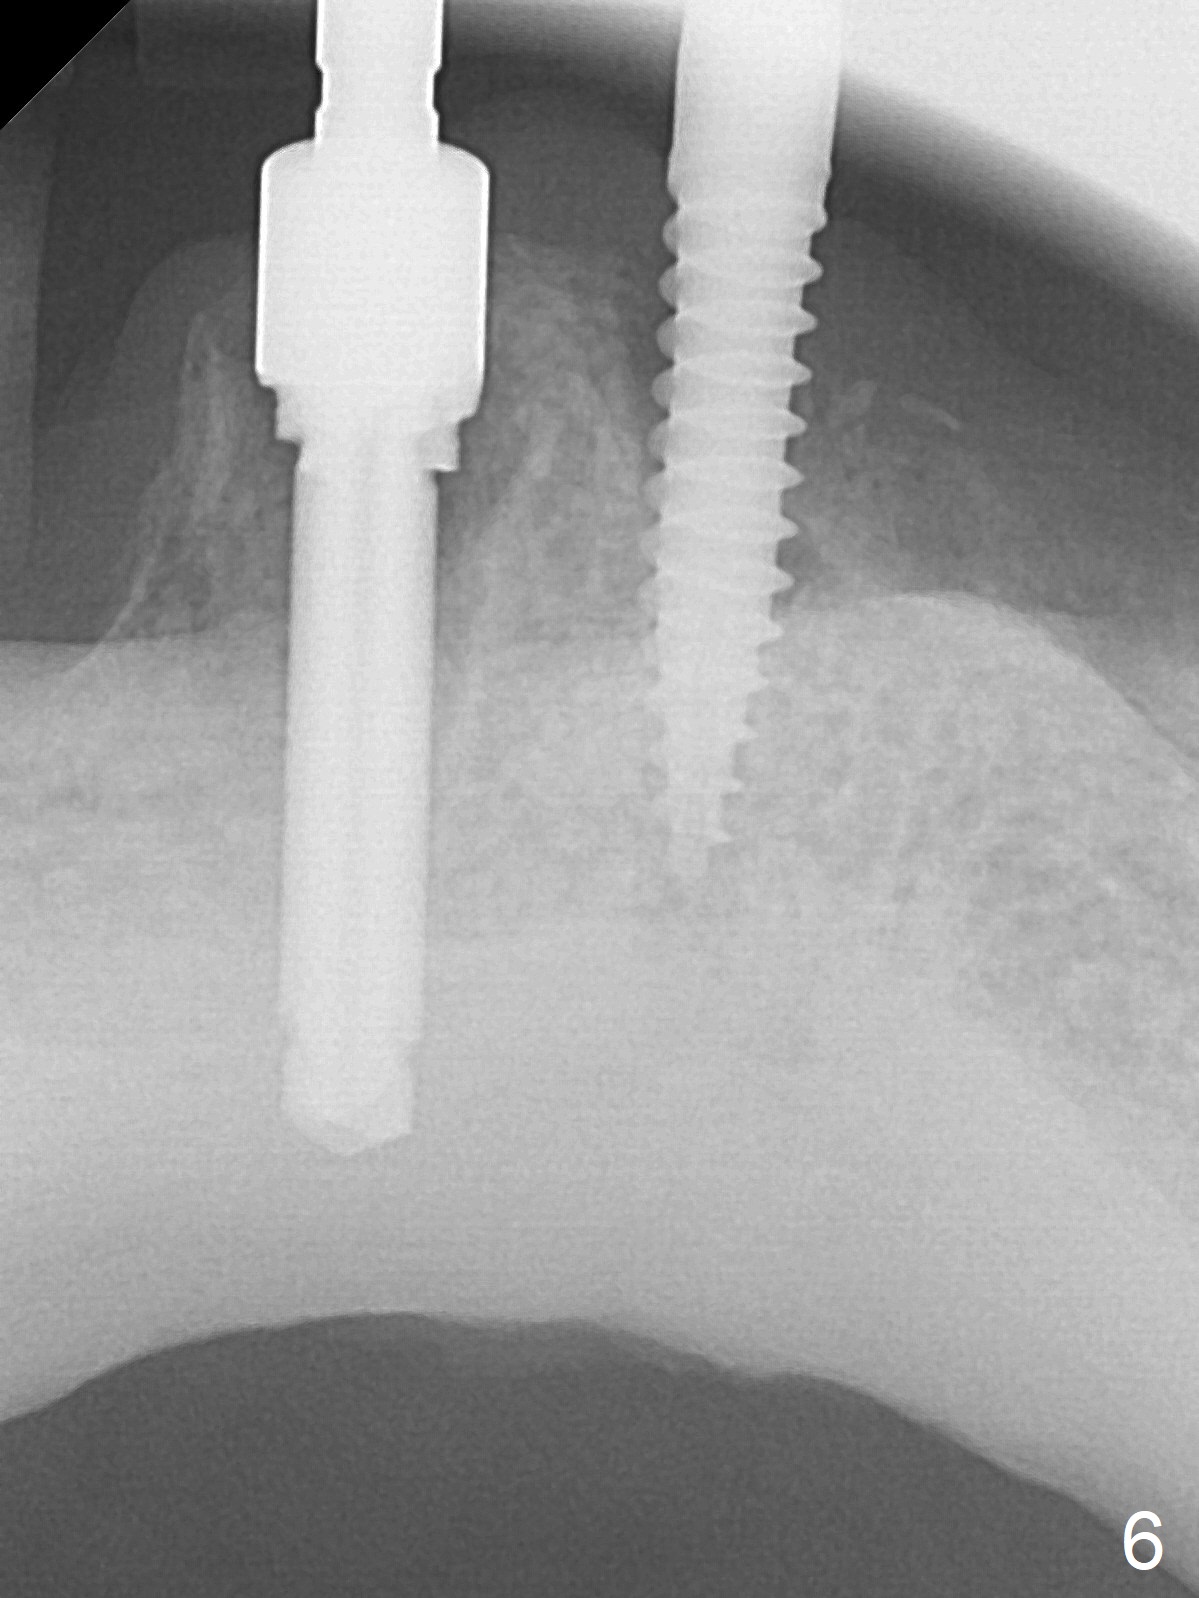

When the patient returns for #26 extraction and immediate implant and #27 RCT, it appears that the tooth #27 with subgingival margin distolingually is non-salvageable (Fig.1). She has dry mouth. Osteotomy is initiated in the lingual slope (Fig.4 red dashed line) of each socket with 1.2 and 2 mm drills for 16 and 19 mm at #26 and 27, respectively (Fig.2,3). The depth at #27 is subsequently reduced, while a 3x14(2) mm dummy implant is placed at #26 (Fig.5,6). A 3.8x13 mm implant is placed at #27 smoothly, while insertion of a 3x16(4) mm definitive implant (by mistake) has resistance (Fig.7). When the depth at #26 increases, there is feeling of perforation. The apex of the implant is truncated prior to reinsertion (Fig.8 >).